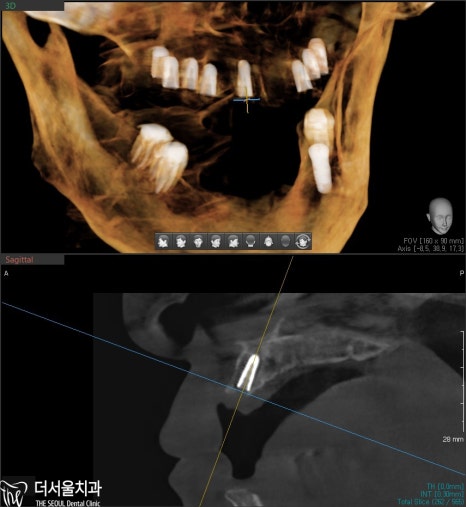

엑스레이 그리고 CT를 통해

한번 더 꼼꼼히 확인을 해서

잘 들어갔는지 봅니다.

계획했던 대로 잘 들어갔네요. ^^

이제 뼈와 잘 붙기를 기다리는데,

수정구치과는 환자분께

“골결합이 잘 이뤄지려면

자극을 받지 않도록 조심해야 된다”며

당부 말씀을 드렸습니다.

(꼭 잘 지켜주세요..)